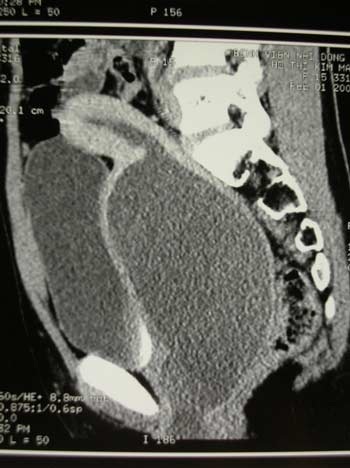

Tại Bệnh viện Nhi Đồng 2, bé H. đã được các bác sĩ chẩn đoán ứ máu kinh trong tử cung âm đạo nhưng do nguyên nhân là bất sản âm đạo. Bé đã được phẫu thuật cấp cứu nhằm giải thoát lượng máu kinh ứ đọng trong nhiều tháng liền và tái tạo lại âm đạo.